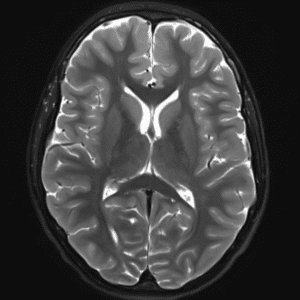

Case #2

Cavernous malformation